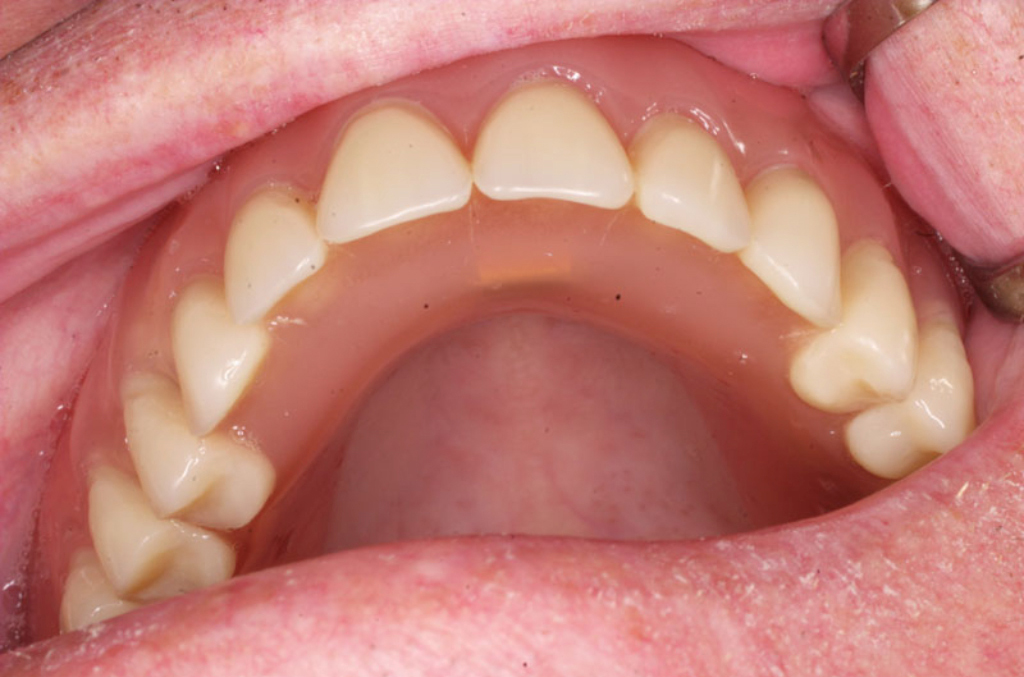

V případě chybění většího počtu zubů v postranních úsecích čelistí je možné ošetření pomocí implantátů, které nahradí ošetření pomocí snímacích náhrad kotvených na zbývajících zubech nebo patře.

Podmínkou je opět dostatečné množství kosti.

Protetické řešení může být pomocí můstku, který je kotvený na implantátech nebo pomocí jednotlivých korunek na implantátech.

V zásadě je možné do těchto můstků zařadit i přirozené zuby, zejména pokud je potřeba tyto zuby ošetřit proteticky – korunkami. Korunky nebo můstky mohou být na implantáty nacementovány nebo přišroubovány.

Zdravé zuby zůstanou zachovány a přitom náhrady jsou pevné, jako na vlastních zubech